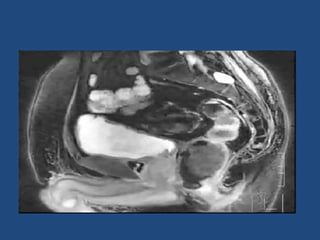

Prostate cancer is the second most common cancer globally, with varying incidence rates influenced by geography and lifestyle changes. In India, prostate cancer cases are rising due to urban migration and increased medical awareness, with current rates approaching those in Western countries. Treatment options vary by stage, including watchful waiting, surgery, radiation therapy, and hormonal treatment, each tailored to patient-specific factors.